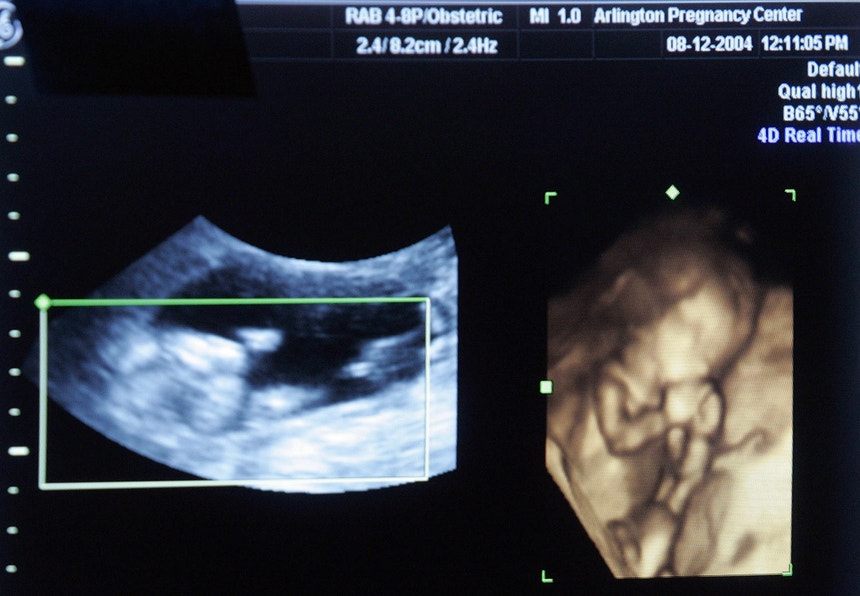

A mãe do bebé que nasceu com malformações graves em Setúbal era seguida no centro de saúde e realizou as ecografias na Ecosado através de credenciais passadas pelo SNS, mas afinal a clínica não tinha qualquer convenção com o Estado.